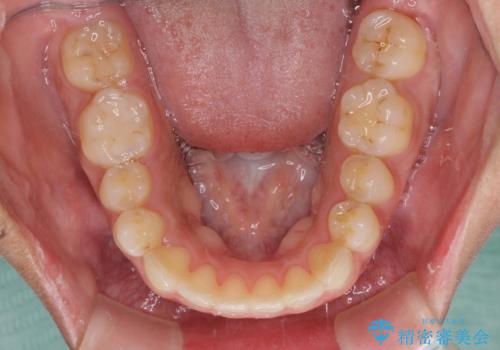

- 上下の前歯のでこぼこを気にして来院された患者様です。

結婚式が近いこともあり、全く目立たない裏側矯正により口元を整えることとしました。

下顎が左側にずれているため、裏側矯正ということもあり咬み合わせを整えるのに時間がかかってしまいました。